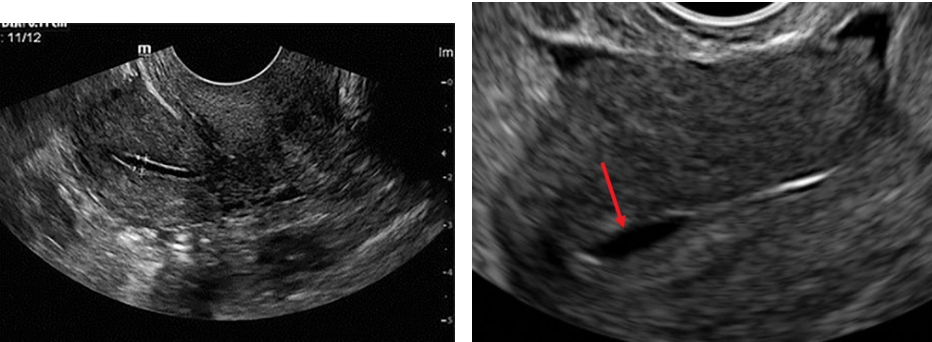

Intrauterine synechiae (endometrial adhesions, Asherman syndrome) are found in women with

posttraumatic or postsurgical histories, including uterine curettage. Synechiae can cause infertility

or recurrent pregnancy loss.

Sonographic Findings: Ultrasonography may demonstrate bright echoes within the endometrial cavity

in this condition.

The diagnosis is difficult unless fluid is distending the endometrial cavity. This is best identified

during the secretory phase when the endometrium is more hyperechoic.

Synechiae are more easily observed in the gravid uterus, where they appear as a hyperechoic band

traversing the uterus from anterior to posterior.

Sonohysterography is an excellent technique for demonstrating adhesions and should be performed in

cases of suspected adhesions. Adhesions appear as bridging bands of tissue that distort the cavity or as

thin, undulating membranes that connect from one side of the uterus to the other. Thick, broad-based

adhesions may prevent distention of the uterine cavity. Adhesions can be divided under hysteroscopy.

Synechiae